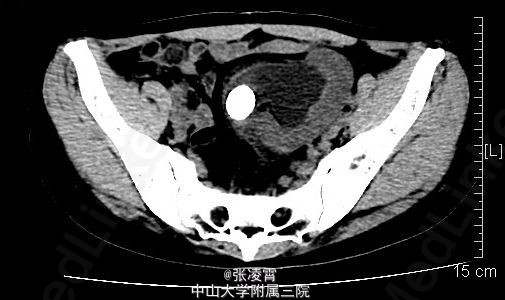

体格检查:体温37.2oC,心率82次/min,呼吸19次/min,血压110/80,皮肤黏膜、巩膜无黄染,全身浅表淋巴结无肿大,心肺未见异常,双肾区无红肿、隆起,左下腹可扪及一边缘清楚的实性包块,呈椭圆形,大小约13x8cm,压痛(+),反跳痛(-)。左肾区叩击痛(-),左肾肋脊点,肋腰点压痛(-),右侧肋脊点、肋腰点压痛(-)。腹平软,左侧输尿管走行区压痛(-),右侧输尿管走行区压痛(-),膀胱区无膨隆,压痛阴性,双侧腹股沟区未触及肿物。 实验室检查:血、大便常规,血生化,胸片,心电图均无明显异常。尿常规:血细胞(++),白细胞(++)尿沉渣白细胞计数252个/μl。 影像学检查:双肾、盆腔螺旋CT平扫+增强扫描+计算机四维成像提示:左肾位于腰4~骶2椎体水平,左肾盂交界处可见一大小约21x18mm高密度结节,边界锐利,左肾盂、肾盏扩张,4条左肾动脉分别起自腹主动脉、右侧髂总动脉及左侧髂内动脉,左肾静脉汇入右肾静脉。左输尿管较对侧短,无明显扩张,双肾形态、大小正常,肾实质未见异常密度影,增强扫描未见强化。右肾盂、肾盏、输尿管无明显扩张,膀胱充盈良好,壁光滑,腔内未见异常充盈缺损。